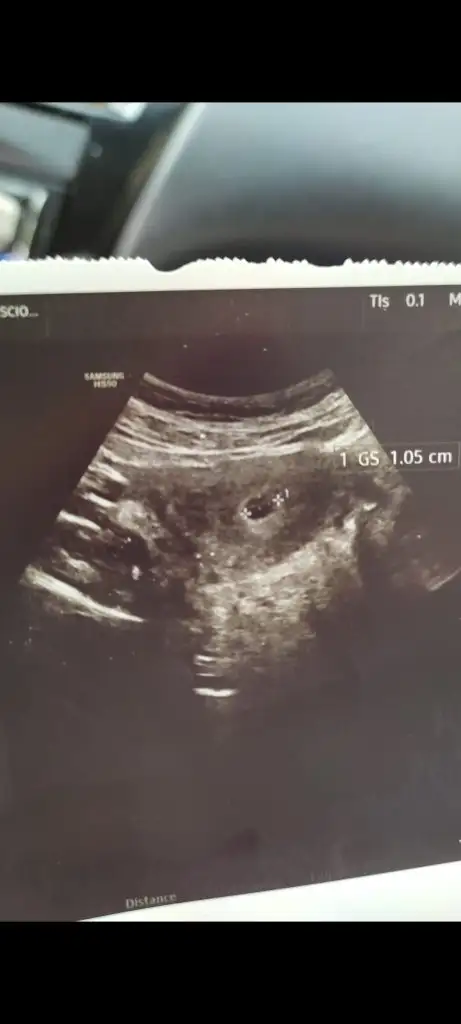

7+1 karından ultrasonSelam Kızlarbir çok kişi gruplardan beni bilir. Yine yetiştim imdatlara

Çoook uzun bir süre araştırma okuma yaptıktan sonra sizlere bu başlığı açtım çevremde tüm gebelere de denedim. Bunun sırrını çözen İnstagramda (isim vermeyim) işi ticarete dökmüş bile.Nub, Ramzi,Çin Rus Japon Takvimleri, Yüzük Yöntemi bir çok şey size sayabilirim.

5 ve 14. haftaya kadar olan ultrason fotolarınızı paylaşın. Vajinadan mı yoksa karından mı çekildiğini ve kaç haftalık olduğunu da mutlaka belirtin.

Not: Tahmin yaptığım anneler cinsiyet öğrendikten sonra lütfen bana geri dönüş yapın